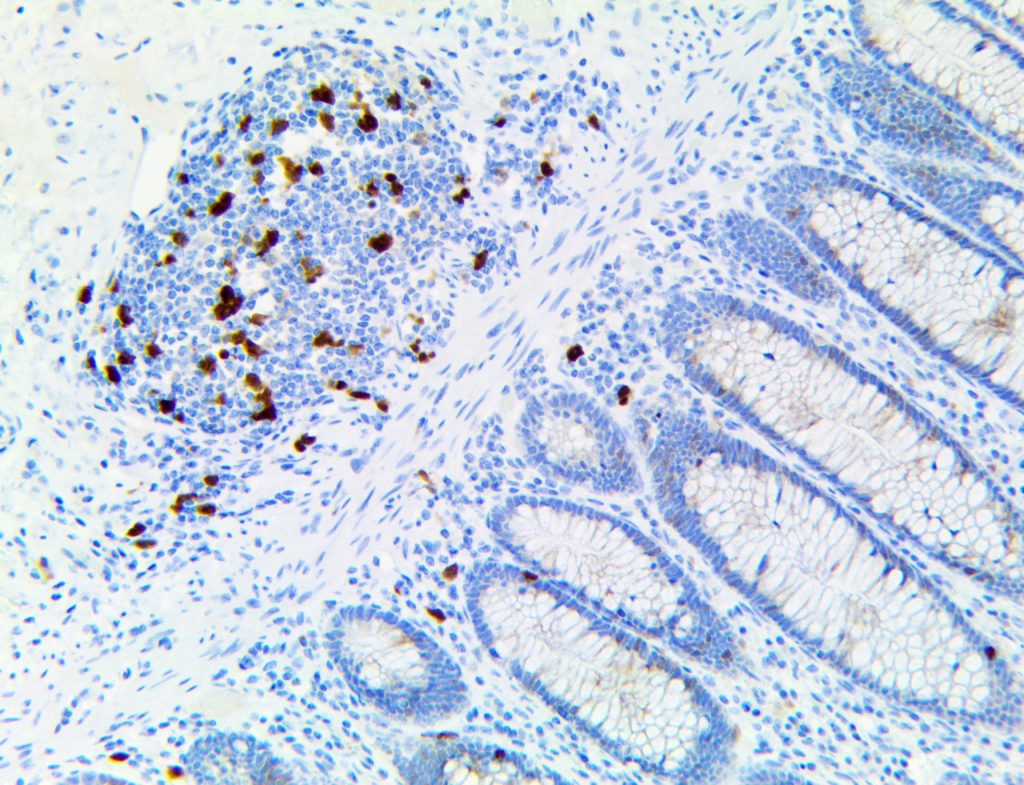

It is the ICU physician who is most likely to witness one of the deadliest manifestations of the abnormal immunological response, the cytokine storm syndrome (CSS). This response is also referred to by some as the cytokine release syndrome (CRS). CSS is characterized by continuous activation and expansion of macrophage and lymphocyte populations, which secrete large amounts of cytokines, causing the cytokine storm. This massive cytokine release is akin to hemophagocytic lymphohistiocytosis (HLH) disease, a syndrome characterized by initial unchecked and persistent activation of cytotoxic T lymphocytes and NK cells.

Clinical and laboratory manifestations of HLH include fever, enlarged liver and/or spleen, neurologic dysfunction, coagulopathy, liver dysfunction, cytopenias (i.e., low levels of erythrocytes, leukocytes, and/or platelets), hypertriglyceridemia, hyperferritinemia, hemophagocytosis, and eventually diminished NK cell activity as the immune system becomes progressively paralyzed. HLH can be familial (primary HLH) or secondary to another disease process (sHLH), such as rheumatic disease, in which it is referred to as macrophage activation syndrome (MAS, characterized by elevated ferritin).